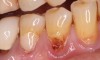

Fig 5. Pre- (Fig 5) and post- (Fig 6) DGV procedure. Note the 7-mm pocket distal to tooth No. 15 before treatment and normal probing depth after treatment. It would have been easier for the restorative dentist to place this crown with increased tooth structure if the tuberosity tissue had been removed previously.

Figure 5

Fig 6. Pre- (Fig 5) and post- (Fig 6) DGV procedure. Note the 7-mm pocket distal to tooth No. 15 before treatment and normal probing depth after treatment. It would have been easier for the restorative dentist to place this crown with increased tooth structure if the tuberosity tissue had been removed previously.

Figure 6

The clinician must determine which of these two harvest techniques should be utilized. Each has its advantages in different situations. For non-wide (buccal-palatal dimension) tuberosities, the DGV technique offers less tissue loss. For wide tuberosities, which are greater than 4 mm in width buccal-lingually and have more CT, the DW technique may be advantageous, as the flap can be approximated and closed with sutures, and this potentially may be more comfortable for the patient. Either technique adequately removes the excess tissue and reduces the pocket. The DGV approach provides a faster tissue harvest and a greater amount of tissue (Figure 5 and Figure 6).